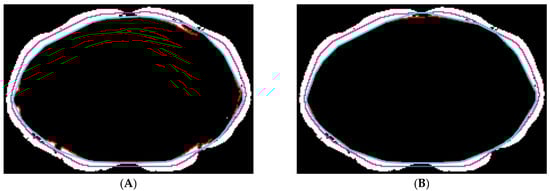

3.2. Inter-Observer Variation

2.5.3. Paraspinal Muscle Segmentation